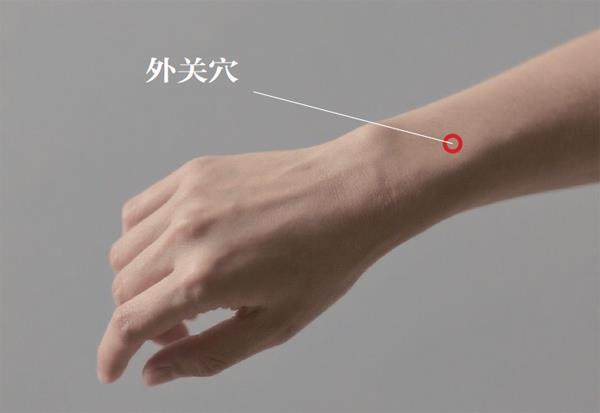

养生益寿 | 按住“蛇七寸”,缓解带状疱疹后遗痛

养生益寿 | 按住“蛇七寸”,缓解带状疱疹后遗痛